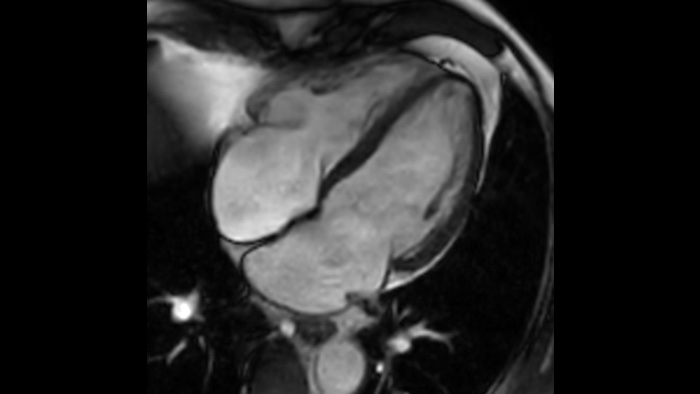

Ahora puede tenerlo todo con Ingenia Ambition. Ofrece la oportunidad de mejorar sus imágenes de resonancia magnética en todos los niveles.

Confianza diagnóstica Ofrece una resolución espacial hasta un 60% más alta en el mismo tiempo de escaneo. 4

Ahora puede tenerlo todo con Ingenia Ambition. Ofrece la oportunidad de mejorar sus imágenes de RM en todos los niveles.

Confianza diagnóstica Amplíe su capacidad de obtener imágenes excelentes en todas las áreas clínicas. Vea cómo se benefician sus compañeros.